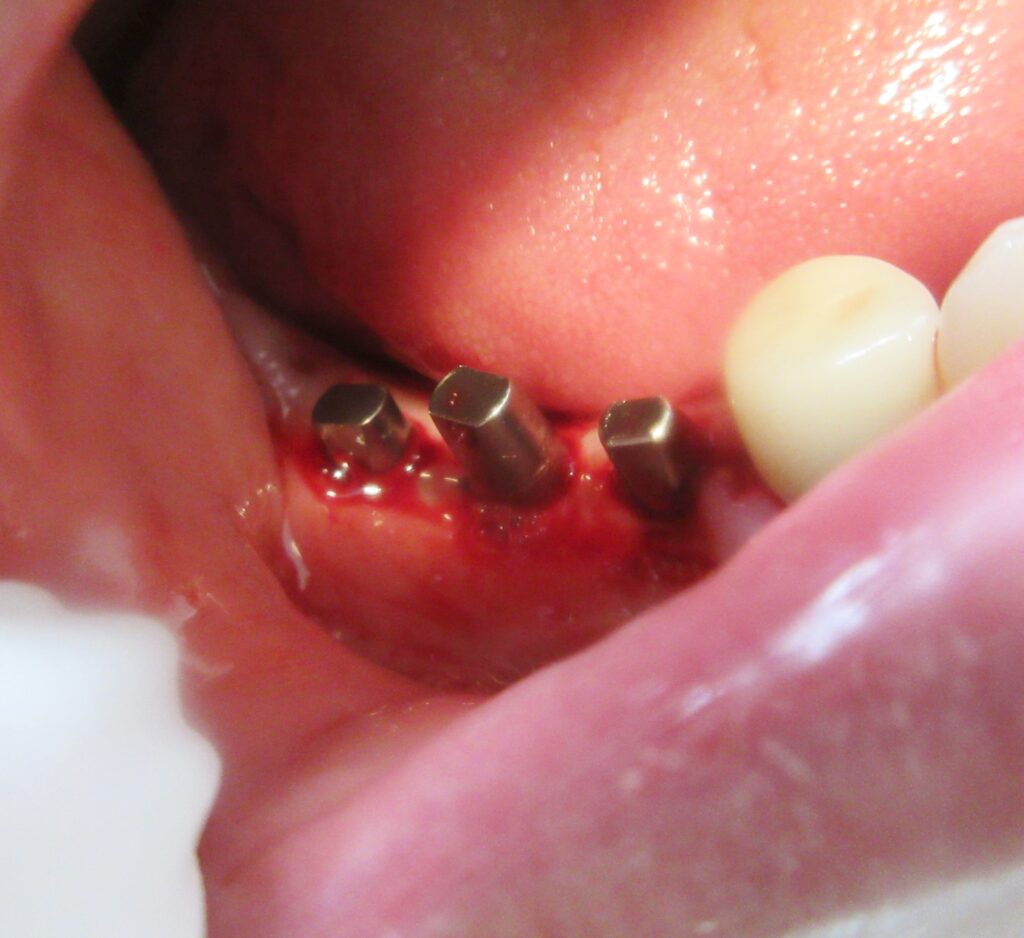

まずは右下5番目の歯茎から骨の部分までを穴開けパンチの要領で穴を開けていきます。

くりぬいた部分の歯肉を取り除き、次は骨に穴を開けていきます。

開けた穴に、専用道具を使ってネジを締めるように長さ2センチ程のインプラントを骨に埋め込んでいきます。

続けて、右上6番目、7番目も同じ工程で植立を行いました。

インプラントオペでは、複数本同時に進行することはせず、1本ずつ同じ工程を繰り返して植立します。